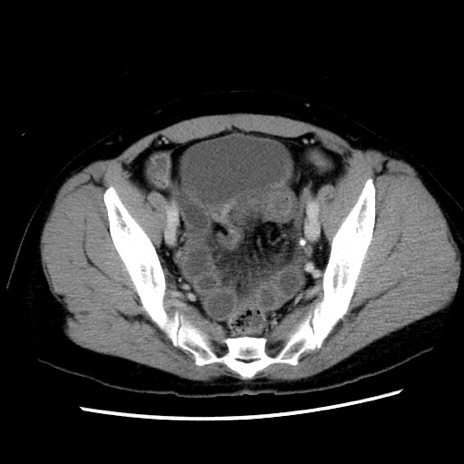

症例10(横断像)

【症例】 50歳代女性

【主訴】 腹痛

【現病歴】前日生レバーを食べた。今朝に排便あり。 昼前に突然発症の腹痛を生じ、当院救急外来を受診した。

【既往歴】 子宮筋腫にてで子宮全摘後

【身体所見】 意識清明、腹部:平坦、軟、下腹部やや左を中心に圧痛・反跳痛あり、筋性防御あり

【データ】WBC 7800、CRP 0.07